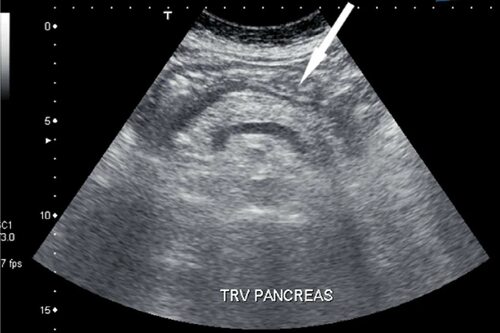

На фотографиях, полученных при УЗИ поджелудочной железы, можно рассмотреть ее анатомическое строение, размеры и структуру тканей. Вы сможете увидеть моменты, которые невозможно обнаружить при обычном осмотре или пальпации.

Фотографии позволяют врачам обнаружить различные патологии, включая опухоли, кисты, дилатацию протоков и другие изменения, которые могут быть связаны с заболеваниями поджелудочной железы.